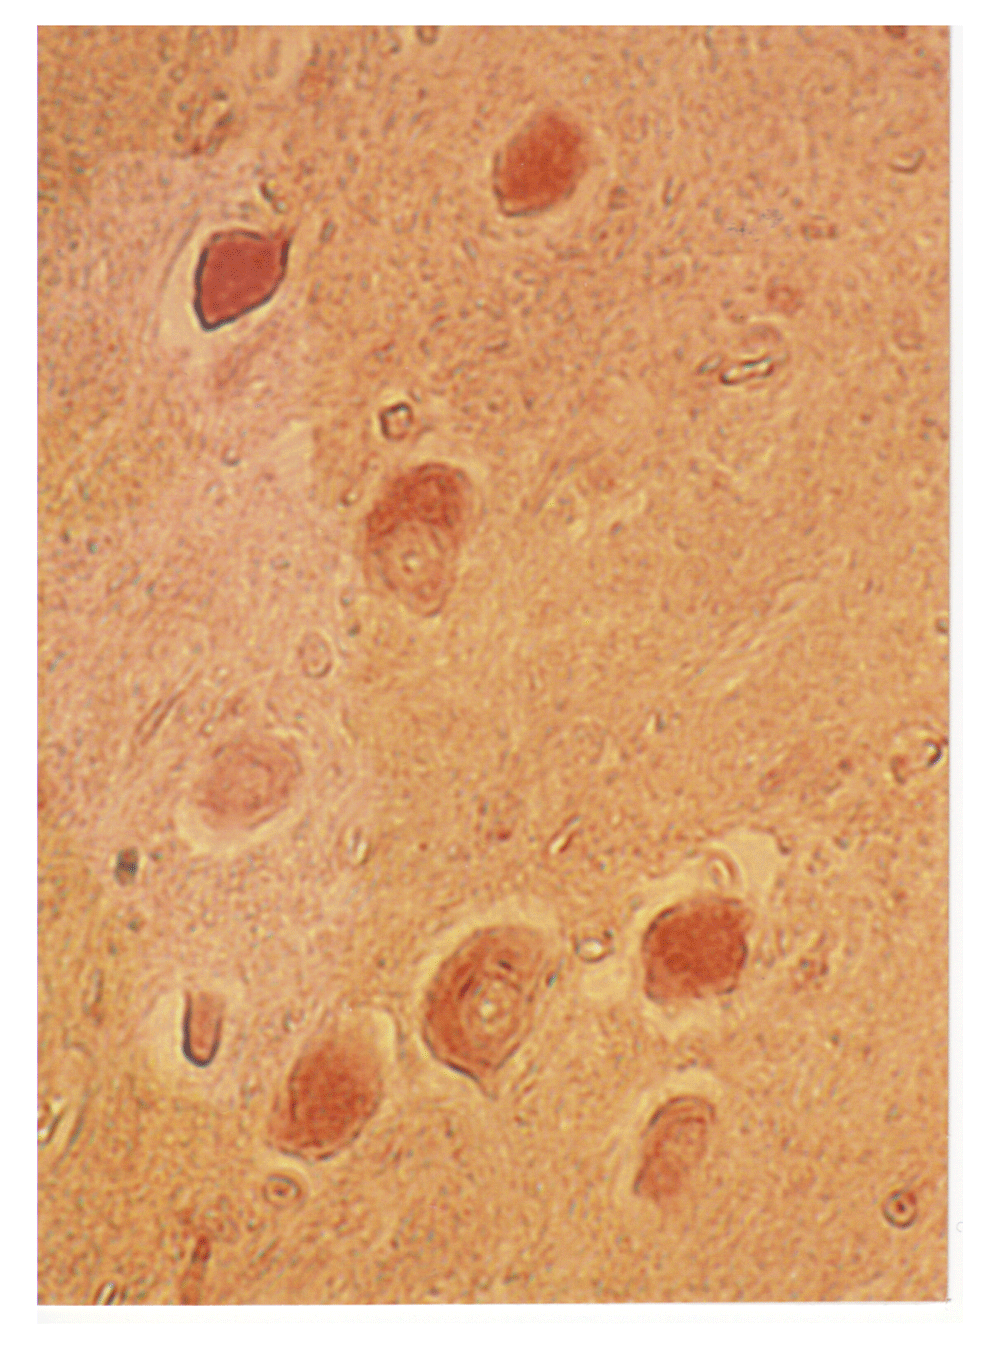

A light microscopy image of an area of the inferior olive of a case of PD is shown that was stained for poliovirus antigen (Figure 16). There is heavy staining of the neurons and light staining of the surrounding neuropil.

Illustrated here is an immunohistochemical image of the inferior olive of a neuron using rabbit anti-polio antibody (see Methods), showing heavy staining of neurons and lighter staining of surrounding neuropil.